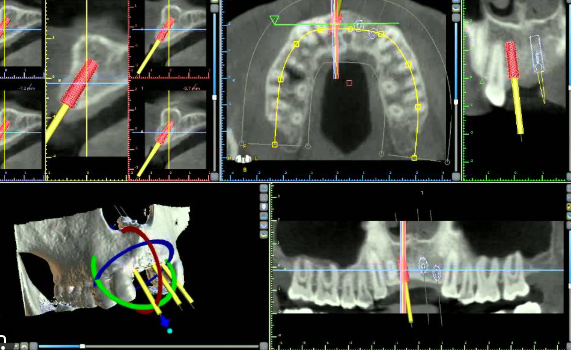

A powerful GPU dramatically improves real-time rendering and 3D segmentation capabilities. GeForce cards provide CUDA support, accelerating AI-based workflows (vital for segmentation of maxilla and mandible).

Advanced graphics cards power smoother, high-fidelity 3D rendering and AI-driven segmentation of the mandible, maxilla, and nerve canals. Software that utilizes GPU acceleration can provide finer, more detailed models for planning, improving the surgeon’s ability to visualize and plan accurately. In practice, this means less risk of missing key anatomic details.

- Segmentation: Software auto-detects and highlights the vital nerve location. For this, an NVIDIA RTX graphics card with a CUDA-enabled profile accelerates rendering and AI-driven segmentation—essential for safely delineating the inferior alveolar nerve.

- 3D Visualization: Dr. Sharma manipulates the maxilla and mandible models in real time, adjusting implant position with no lag, thanks to at least 16GB RAM and dedicated GPU.

- Complex Segmentation: For segmenting remaining teeth and jawbones, CUDA acceleration from the graphics card ensures smooth rendering of even full-mouth datasets.